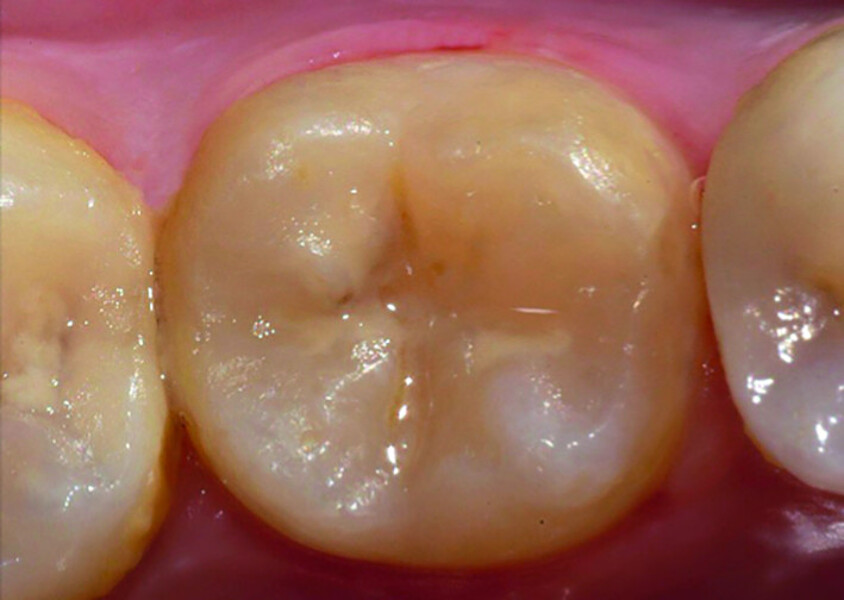

Fig. 1: Pre-op occlusal view.